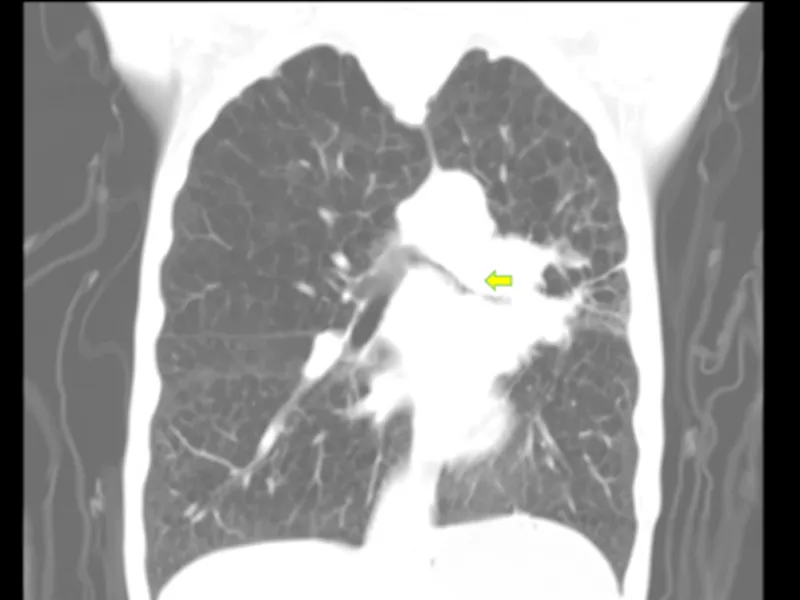

▲左肺门-纵隔肿块(黄色标记狭窄区域)

术中发现左主支气管黏膜严重肿胀、增粗,左肺上叶支气管被新生物完全堵塞,左肺下叶支气管极重度狭窄。手术团队运用激光技术成功消融了管腔内的新生物,扩大了左肺下叶支气管管腔,使得4.2mm的气管镜能够自由通过,有效缓解了患者的气道阻塞症状。